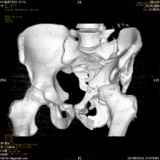

Повреждение вертлужной впадины 2,5 мес. |

Уважаемые коллеги! Хотелось бы услышать совет по тактике лечения представлленого больного.Поступил после лечения в одном изотделений области. Травма 2,5 месяца назад. После выведенияиз шока был произведен остеосинтез перелома бедра, предплечья, до перевода к нам проводилосьвытяжение по оси шейки бедра за стержень, введенный в большой вертел. На сегодня деформацияригидна, клинически мобильности не определяется. Заранее признателен. P.S. Данный вид травм не включен в перечень "высокотехнологичных операций", направить длялечения по квотам Минздрава очень сложно.

Это обзорные и косые снимки

Привет, Леонид. Оскольчатый высокий двухколонный перелом в такие сроки трогать не надо, т.к. это про такие переломы сказано: "кто с ножом на Ж. пойдет тот в ней и останется...".